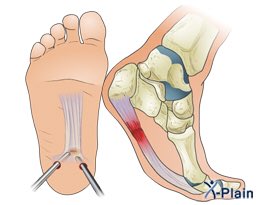

¿Y la cirugía que? Pues podemos hacer dos cosas diferentes. La más lógica, actuar sobre la fascia. Se hará una liberación de la misma de forma abierta, percutánea o artroscópica si no notamos mejoría con el tratamiento conservador pasados 9-12 meses.